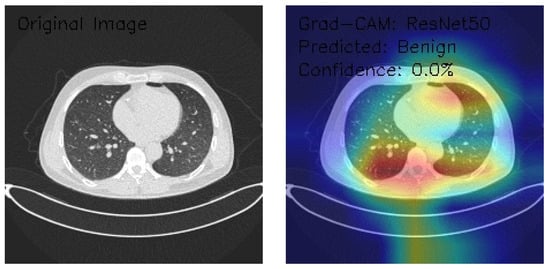

ResNet50 Deep Learning Model

The three axial chest CT images were analyzed using a state-of-the-art ResNet50 deep learning model, a widely recognized convolutional neural network architecture known for its robust performance in image classification tasks. Grad-CAM visualization was employed to gain insights into the model’s decision-making process. This technique provides a detailed heatmap overlay on the original images, highlighting the regions of interest that contributed most significantly to the classification decisions. This combined approach enables accurate classification and offers interpretability, ensuring that the underlying rationale for the model’s predictions can be understood and validated in a clinical context.

Figure 6 demonstrates normal lung parenchyma with a central mediastinal structure. The Grad-CAM heatmap shows predominant activation in the right lateral lung field, indicated by the yellow-red colorization. The model classified this as Benign with minimal confidence (0.0%), suggesting potential limitations in the model’s decision-making process.

Figure 6.

Grad-CAM visualization using ResNet50 for lung CT analysis. (Source: author’s analysis from data, 2024).

Figure 7 shows that the image reveals similar anatomical structures with slightly different density patterns. The Grad-CAM activation is most prominent in the central and right posterior regions, displaying intense activation patterns (yellow-red areas). Despite the visible features, the model again classified this as Benign with 0.0% confidence, indicating potential model uncertainty.

Figure 7.

Grad-CAM visualization using ResNet50 for lung CT scan showing benign prediction. (Source: author’s analysis from data, 2024).

Figure 8 shows an image of distinct parenchymal patterns, particularly in the central and peripheral regions. The Grad-CAM heatmap demonstrates strong activation in the central mediastinal region, extending into the right lung field. Notably, this was classified as Malignant with 0.0% confidence, representing a shift in classification despite the low confidence score.

Figure 8.

Grad-CAM visualization using ResNet50 for lung CT scan with benign prediction. (Source: author’s analysis from data, 2024).

This analysis evaluates the application of ResNet50 with Grad-CAM visualization on three axial chest CT images, focusing on the model’s regions of interest and classification confidence. Grad-CAM heatmaps highlight consistent activation in central thoracic and lung structures, with bilateral asymmetry and variable peripheral attention. Image classifications include two Benign (Images 1 and 2) and one Malignant (Image 3), all with 0.0% confidence, indicating significant uncertainty in the model’s predictions. These results reveal model calibration and reliability issues despite its ability to identify relevant anatomical features. To enhance clinical applicability, recommendations include recalibrating the confidence scoring system, expanding the training dataset, incorporating ensemble methods, and validating results with expert radiologists. This analysis underscores the need to refine the model further to improve its diagnostic reliability and confidence.